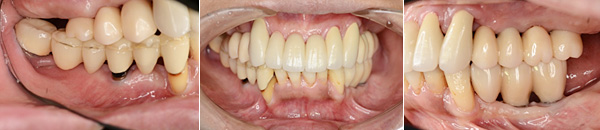

初診時

治療後